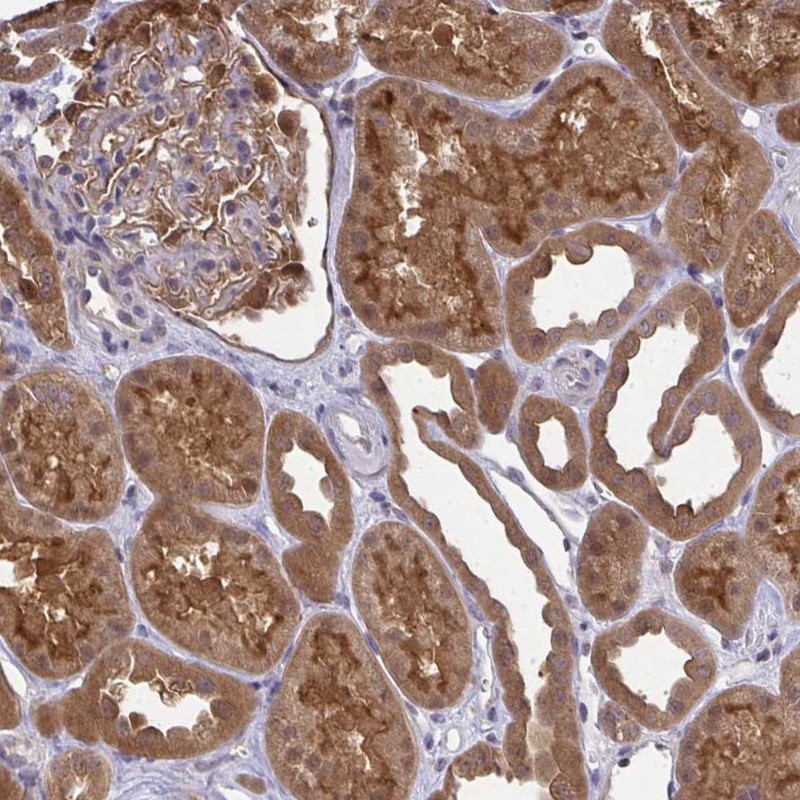

Immunohistochemical staining of human kidney shows strong cytoplasmic and membranous positivity in cells in tubules.